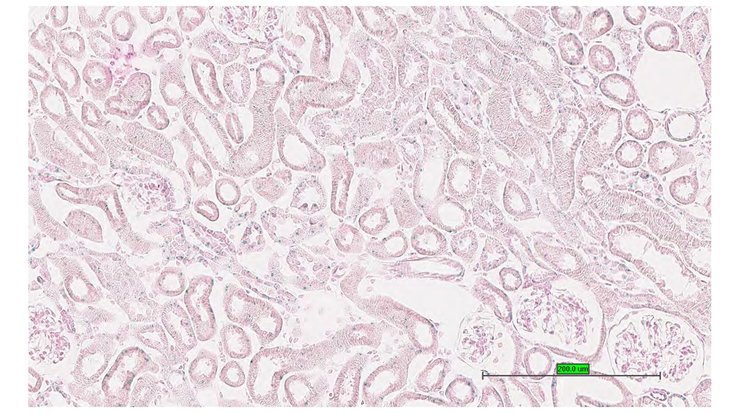

Specimen UC Davis_1882580: postnatal adult; Phc3tm2b(KOMP)Wtsi/Phc3+ (more )

Structure Level Pattern Image Note

TS28: metanephros Present UC Davis_1882580 kidney

Specimen UC Davis_1882581: postnatal adult; Phc3tm2b(KOMP)Wtsi/Phc3+ (more )

TS28: metanephros Present UC Davis_1882581 kidney

Specimen UC Davis_1882582: postnatal adult; Phc3tm2b(KOMP)Wtsi/Phc3+ (more )

TS28: metanephros Present UC Davis_1882582 kidney

Specimen UC Davis_1882635: postnatal adult; Phc3tm2b(KOMP)Wtsi/Phc3+ (more )

TS28: metanephros Present UC Davis_1882635 kidney

Specimen UC Davis_1882636: postnatal adult; Phc3tm2b(KOMP)Wtsi/Phc3+ (more )

TS28: metanephros Present UC Davis_1882636 kidney

Specimen UC Davis_1882637: postnatal adult; Phc3tm2b(KOMP)Wtsi/Phc3+ (more )

TS28: metanephros Present UC Davis_1882637 kidney